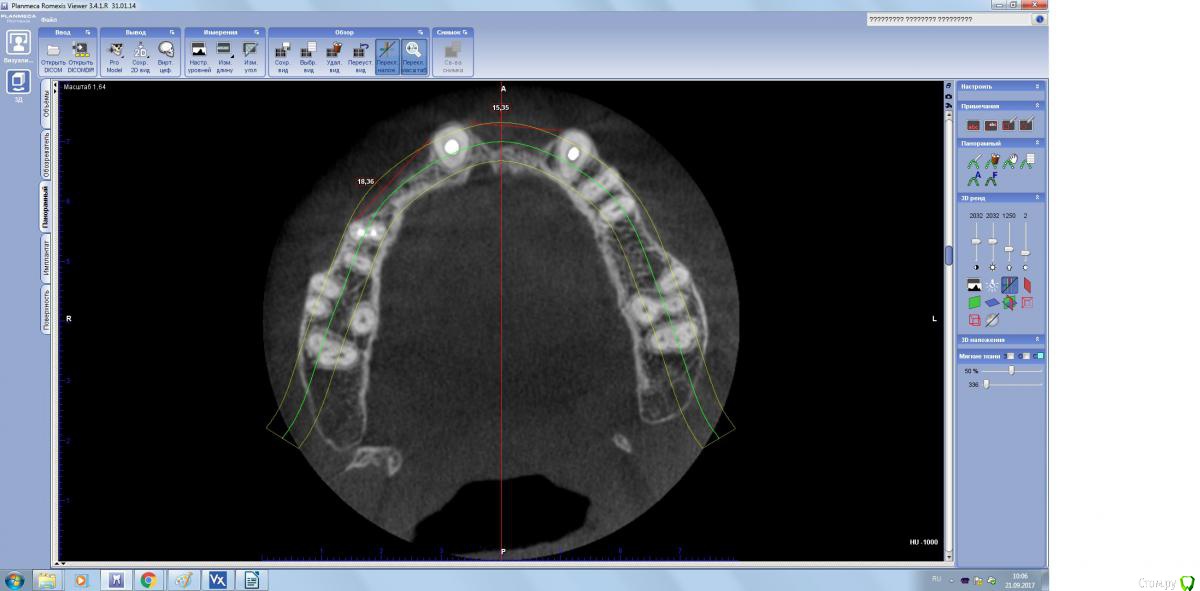

Пришел парнишка на имплантацию, но как видите ряд проблем присутствуют.

Хочу восстановить ламинатами... и есть ряд вопросов.

1. Можно ли восстановить сначала один сегмент а потом второй сегмент, почему спрашиваю, если идти двух этапно, какой дизайн разреза должен быть во второй раз и как мобилизоваться?

2.Надо ли перекрывать ССТ?

3. Можно ли пока оставить зубы? они конечно негодные, но хоть как то помогут мне в пластике...